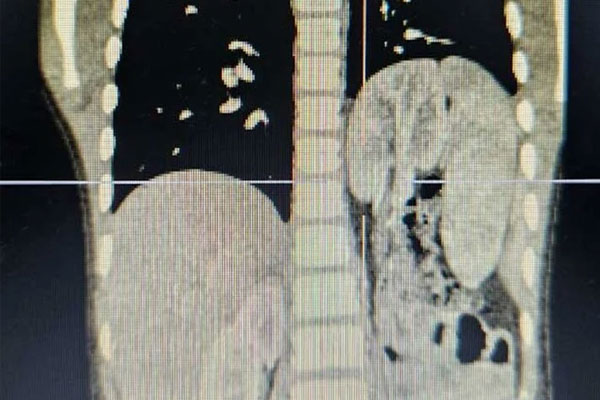

Bé trai nhập viện sau nhiều lần bị nhiễm khuẩn hô hấp, xuất hiện cơn đau tức ngực kéo dài. Qua thăm khám, chụp X-quang, cắt lớp vi tính (CT) kết quả hình ảnh cho thấy, bé bị thoát vị cơ hoành trái, với các cơ quan nội tạng gồm lách, đại tràng, ruột non, đặc biệt là thận trái bị lạc chỗ trong lồng ngực.

Phim chụp cắt lớp vi tính cho thấy các cơ quan thoát vị trở lại vị trí giải phẫu bình thường, cơ hoành liền tốt và phổi trái của bé nở đều. Chức năng thận trái sau khi trở về ổ bụng cũng được đánh giá không có bất thường. Bệnh nhi hồi phục ổn định và được xuất viện sau 7 ngày.